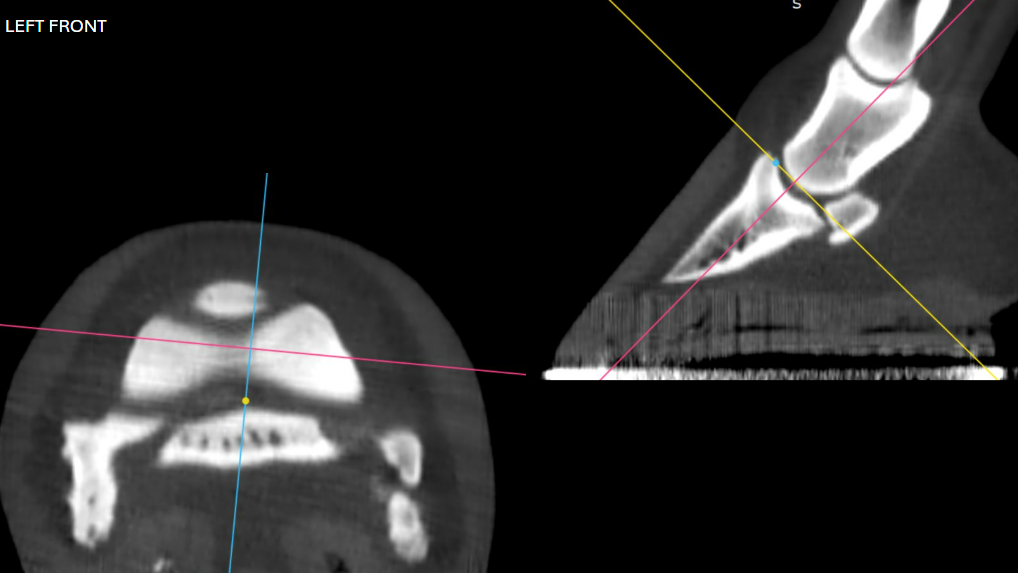

CT revealed an abnormality in the RF fetlock that was not visible on prior radiographs. The RF fetlock joint was injected with triamcinolone and hyaluronic acid (HA). If further treatment is required, biologics or polyacrylamide gels are recommended over corticosteroids. In cases where these treatments do not restore function, placing a screw distal to the subchondral defect may be considered.

Right Front shown above

• Radiographs initially suggested pathology in the coffin and pastern joints, which was confirmed by CT.

• However, radiographs did not reveal any abnormalities in the fetlock, whereas CT clearly identified the lesion.

• Adjusting image brightness and contrast further highlighted the lesion.